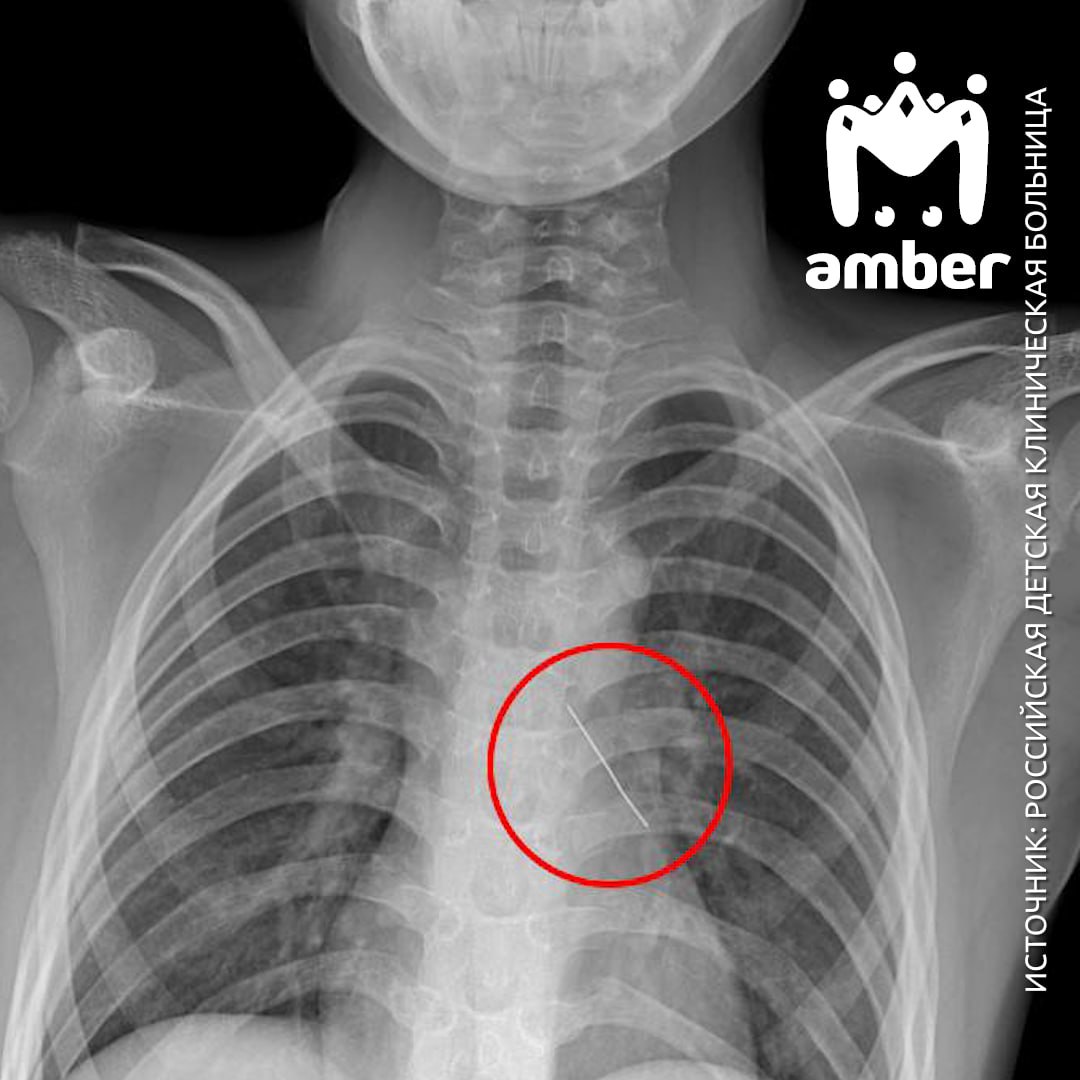

Изогнутая булавка пробила бронх 11-летнего мальчика из области — он просто её вдохнул.

Сначала железку пытались извлечь в Калининграде — не вышло. Поэтому бортом санавиации паренька доставили в Москву. Он мог говорить только шёпотом, жаловался на сильные боли в груди. Рентген показал: булавка обосновалась в нижней доли левого бронха.

Хирурги удалили её оптическими щипцами (погуглите, они суперинтересно выглядят) — прямо за головку. Мальчик в порядке, уже дома, под наблюдением местных врачей.